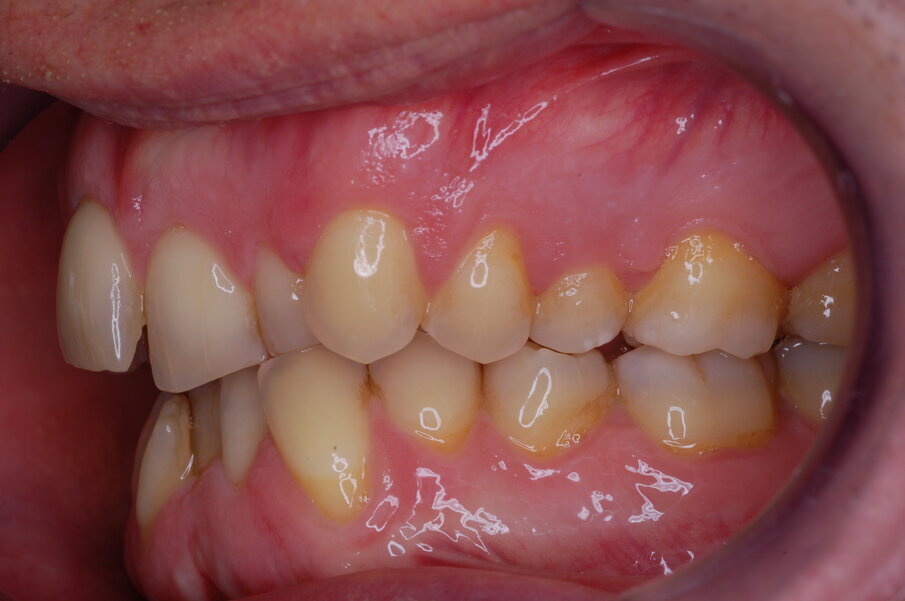

Diagnosi ed eziologia Un uomo sano di 39 anni si è presentato nel nostro studio ortodontico lamentando un aspetto dentale poco attraente e la paura della chirurgia ortognatica proposta da un altro ortodontista. Clinicamente, il profilo del paziente era rettilineo e la vista frontale non mostrava alcuna asimmetria facciale. L’esame funzionale non ha rivelato alcuna deviazione mandibolare o riduzione dei movimenti. Il paziente non aveva dolori articolari e non sono stati rilevati rumori articolari. Era presente una lieve occlusione molare bilaterale di Classe II, un morso aperto e un grave affollamento in entrambe le arcate. L’affollamento era particolarmente grave nell’arcata mandibolare, sebbene mancasse l’incisivo centrale mandibolare destro. Gli incisivi mascellari erano di piccole dimensioni, suggerendo una discrepanza dell’indice di Bolton se fossero stati presenti tutti e quattro gli incisivi mandibolari. Erano inoltre presenti un morso incrociato nella regione dell’incisivo laterale superiore sinistro e una grave rotazione distale del secondo premolare mandibolare sinistro (Figg. 1-8).

Figg. 1-8_Fotografie facciali e intraorali pre-trattamento.